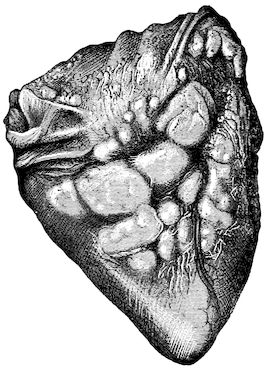

Fig. 3.—Pig suffering from osseous cachexia (fourth stage).

114. The fourth phase, or period of osteomalacia, i.e. softening of the bones, is also the last. It is rarely seen in large animals like horses and oxen, because accidents so often accompany the preceding stages and necessitate slaughter; but it is common in goats and pigs.

In this phase the bones become elastic, soft and depressible, yielding to the pressure of the operator’s fingers.

Fig. 4.—Deformity of the face in the horse shown in Fig. 2.

The flat bones are particularly liable to this change, which is common to domesticated animals. The bones of the head are the first to suffer; later those of the pelvis. The lower jaw becomes swollen, particularly about the centre of the branches which may attain three, four, or five times, their normal thickness.

The depression in the submaxillary space disappears. The upper jaw undergoes similar changes, becoming deformed and thickened until the cavities of the sinuses and the hollow appearance of the palate are lost, while the face is so changed that it cannot be recognised as that of a horse, goat, etc.

The molar teeth are almost buried, their tables alone being visible at the bottom of a depression, the edges of which rise above the neighbouring parts (pig).

Mastication is clearly impossible, the jaws appear paralysed, the muscles powerless, and only swallowing is possible, a fact which explains why life is only prolonged to this stage in animals which can be fed with a spoon or bottle (pigs and goats). The bones of the cranium, although greatly changed in texture, are always less deformed than those of the face.

The changes are such that it is often easy with a mere post-mortem knife to cut the head completely in two. Osseous tissue, properly so-called, has disappeared.

All the constituent tissues, with the exception of the skin and muscles, i.e., the bone, periosteum and aponeuroses, have the appearance and consistence on section of the fibro-lardaceous tissue seen in chronic inflammation.

Fig. 5.—Head of a pig suffering from osseous cachexia.

Fig. 7.—Osseous cachexia: softening of the maxillæ.

Fig. 8.—Transverse section through the middle region of the face in a pig suffering from osseous cachexia.

18In the final stages, the bones may be cut with a knife, and a time arrives when bony tissue seems completely to have disappeared; thus, as shown in Fig. 8 herewith, it was possible to cut the entire head of a pig into thin slices without the slightest difficulty. All parts of the head had been affected by the softening change.

From the chemical point of view, the diminution in mineral salts and in phosphate of calcium has long been recognised, but the degree of this change varies according to the phase. In human beings the proportions have been estimated as follows: Normal bone, 50 to 80 per cent. of phosphate of calcium; bone in persons suffering from osteomalacia, 5 to 20 per cent. of phosphate of calcium. The changes in the ossein have not been carefully studied. We only know that histologically the ossein becomes fibrillar, and that chemically it no longer retains its normal composition.